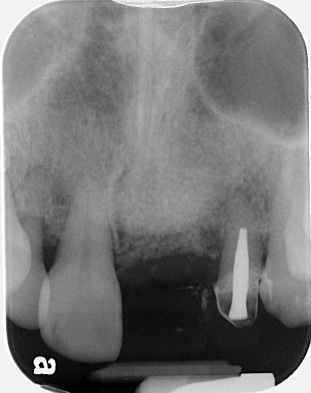

找到術前的 X 光片,原來是因為 #21 有根尖囊腫及 root perforation,無法保留,前一位 GP 醫師選擇把 #21 拔除後,轉來給 tof 評估

tof 在這邊,只先讓大家看看什麼叫做「沒有 buccal plate」。